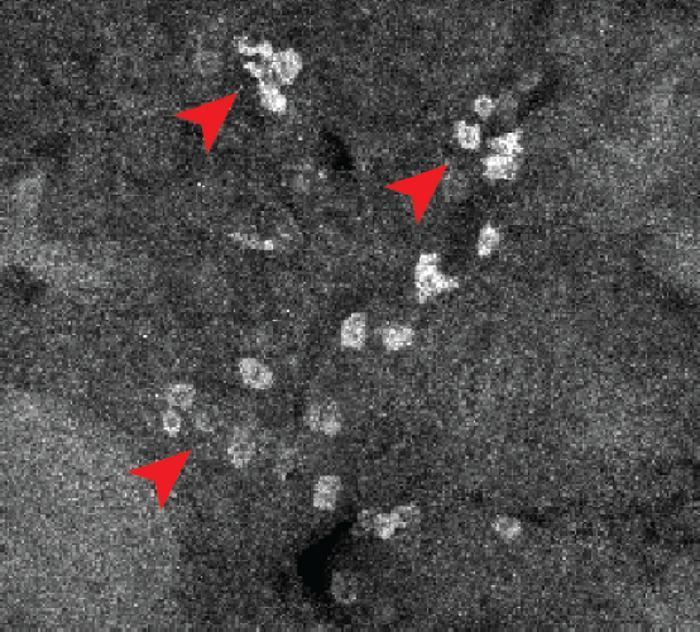

新技術“照亮”藥物與單細胞結合位點,有助發現藥物副作用